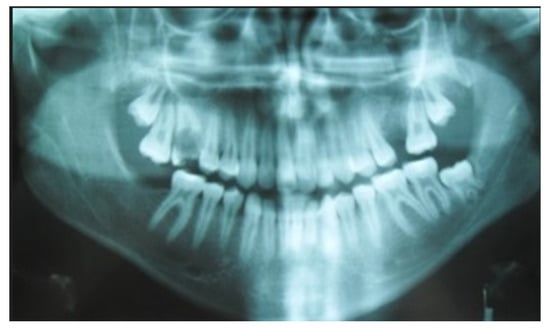

2. Case Report Presentation